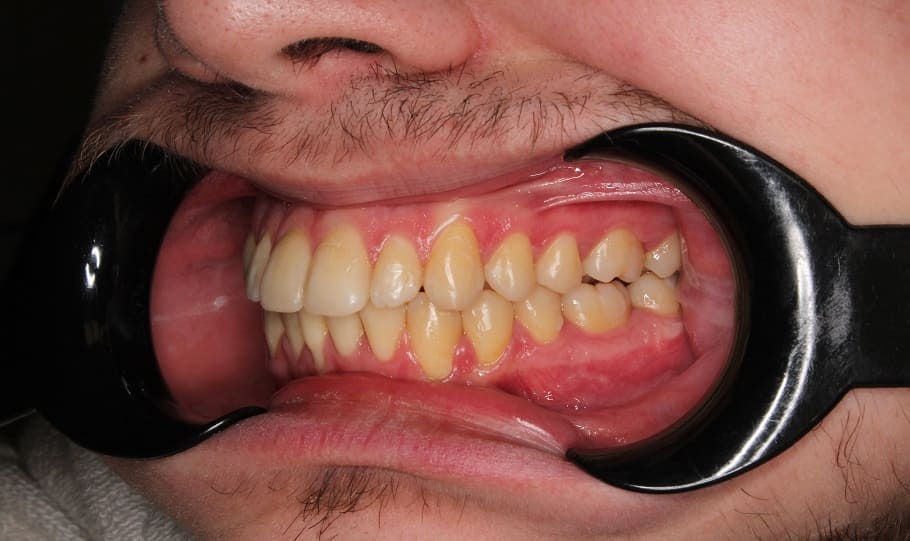

Лечение на самолигирующей брекет-системе Н4. Ортодонтическое лечение заняло 2 года.